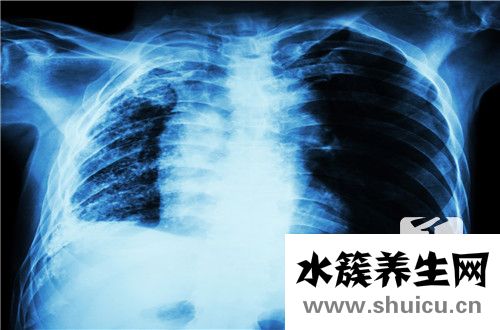

肺栓塞是由各種栓子脫落引起的。生病后會出現體力不支、面色蒼白、出汗、呼吸困難、胸痛等癥狀。部分患者肝切除術后肺栓塞發生率高。他們剛剛解決了肝臟的問題,出現了肺部的癥狀。當然,他們非常關心待遇。那么,肝切除術后肺栓塞怎么辦?下面來討論解決方案。

切肝手術后肺栓塞要依據病人的風險水平來挑選治療方法,針對低危及其中危的病人臨床醫學需要用抗凝劑來開展醫治,常見的抗凝劑臨床醫學上關鍵便是低分子肝素或是一般肝素引入。而針對上位的肺栓塞病人而言,需要立即開展栓塞治療,例如鏈激酶、鏈激酶或是是RTPA溶血栓的實際效果是十分非常好的。

依據栓子尺寸以及堵塞肺動脈的水平,臨床癥狀有輕和重之分:

發病忽然,病人忽然產生模糊不清原因的體力透支、臉色蒼白、出虛汗、呼吸不暢者、胸口痛、咳嗽等癥,乃至昏厥、咯血。大腦缺氧病癥:病人極其心神不寧、害怕、惡心想吐、抽動和昏迷。亞急性疼痛:胸口痛、肩背痛、頸部痛、心前區及上腹部疼痛。總而言之,依據栓子的尺寸及堵塞的位置主要表現各有不同,但昏厥可能是急性肺栓塞惟一或先發病癥。

依據臨床癥狀可分成卒死型;亞急性心源性休克型;亞急性肺心病型;肺梗死型;突發模糊不清原因型。

2、臨床癥狀

大的動脈栓塞可出現亞急性右心衰竭的病癥,乃至猝死。心跳過速,乃至有左室期奔馬律,肺動脈第二音較為亢奮,主動脈瓣膜及肺動脈瓣有第二音瓦解,休克、紫紺、頸靜脈怒張、肝大。肺臟濕羅音、胸膜摩擦音、喘氣音及肺實變的臨床癥狀。